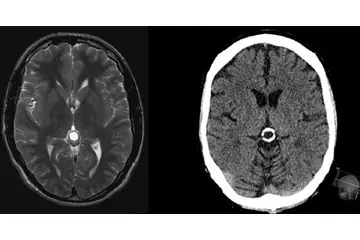

Beyinde kitle ameliyatı, genellikle tümörler, kist veya diğer anormal oluşumların cerrahi olarak çıkarılması amacıyla yapılan bir işlemdir. Bu tür bir ameliyat, beyin dokusuna doğrudan müdahale gerektiği için belirli riskler taşır ve sonrasında hastalar için çeşitli zorluklar ortaya çıkabilir. İşte bu makalede, beyin kitle ameliyatının riskleri ve sonrası hakkında detaylı bir inceleme yapılacaktır. 1. Beyin Kitle Ameliyatının Riskleri Beyin kitle ameliyatı, birçok risk barındırır. Bu riskler arasında şunlar bulunmaktadır:

4. Potansiyel Komplikasyonlar Ameliyat sonrası komplikasyonlar, hastanın genel sağlığını etkileyebilir. Bunlar arasında: